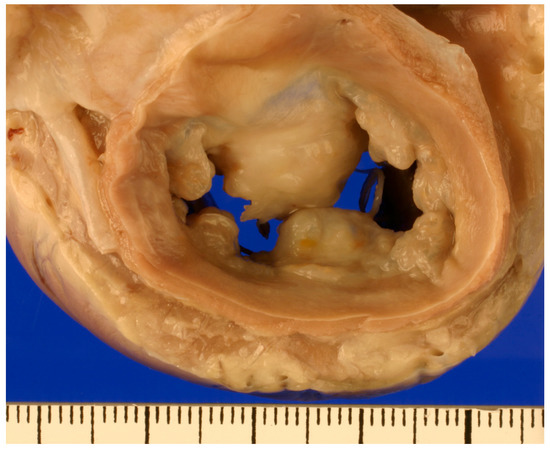

1. Introduction

2. Diagnosis